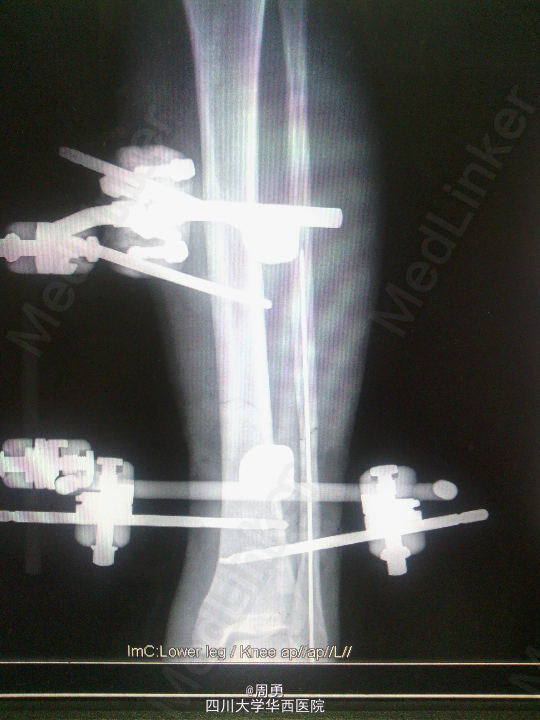

闭合穿针复位腓骨在开放性骨折中应用和意义

某些腓骨骨折常无需处理,但在开放性骨折一期处理创面同时,为了达到恢复肢体长度、条件允许情况下最大可能复位骨折、简化二期手术目的,某些时候复位腓骨并闭合穿克氏针对骨折复位和固定会有一定帮助,选几年前2个博士住院总期间X片示意,欢迎大家交流。